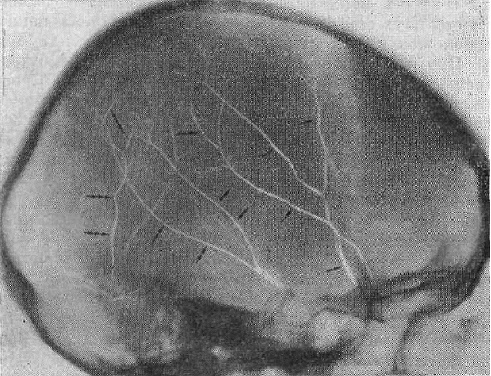

Сосудистая борозда

Сосудистая борозда 108 фото